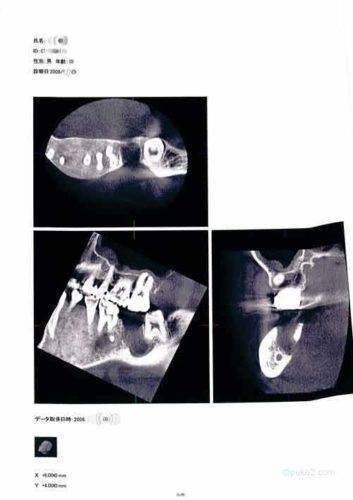

そこで、もう一枚みてもらいましょう。

先ほどのレントゲン画像を上から撮ったものを・・

この画像の方が歯槽骨が溶けていることがわかるかもしれません。抜いた7番の歯の空洞はともかく、歯槽骨のラインが思いっきりへこんでおります・・。いやはや怖いですね。

今回の記録帳のレントゲンの画像ですが、これはキノコ隊長自身のものです。よそからの流用などではありません。まぁ、データとして手に入れたものではありませんので、紙に印刷したものをスキャンして画像にしたものです。

この画像の入手先は、今も通う歯医者さんではありません。実は、この歯医者さんの先輩のところです。左下奥歯(7番)を抜歯したあと経過観察をすることになったことは、記録帳内にもあったので覚えているかと思います。経過観察中にこんなことありましたよ。

この機器というのが立体的にレントゲン撮影ができるとうもので、ちょっとスペイシーな感じのするものだったのです。で、その先輩歯医者さんが、

「データ(CD-ROM )は後輩くんに渡してね~、でこっちは印刷したから記念品(笑」

とくださったものです。